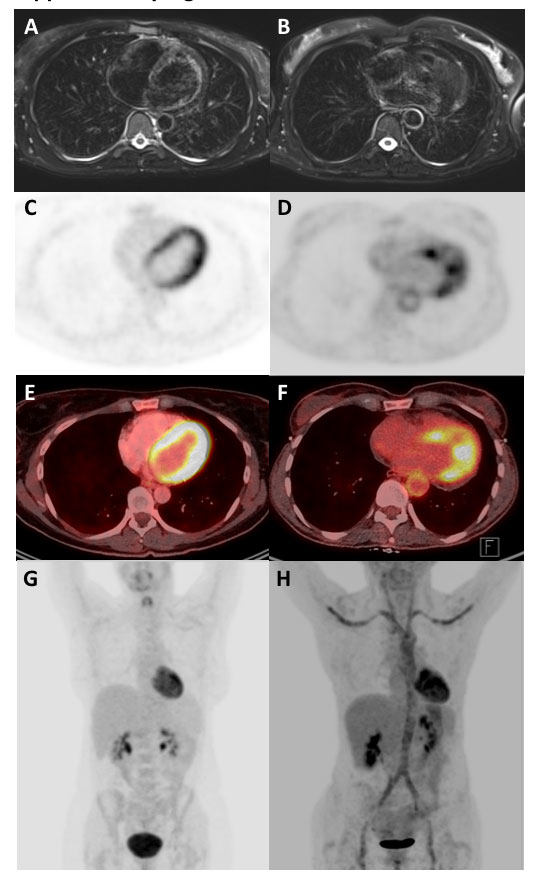

Figure 5 Comparison of vasculitis and normal findings. Panels A, C, E, and G are from a patient without vasculitis. Panels B, D, F, and H show the same patient as in figure 3. T2-weighted fat-suppressed magnetic resonance imaging (PROPELLER sequence) (A, B), 18F-fluorodeoxyglucose positron emission tomography attenuation corrected (C, D) fusion (E, F) and maximum intensity projection reconstruction (G, H) are shown.

Examples of PET and MRI findings in patients with vasculitis compared to normal findings of healthy controls are shown in supplementary figure S1 in appendix 1.